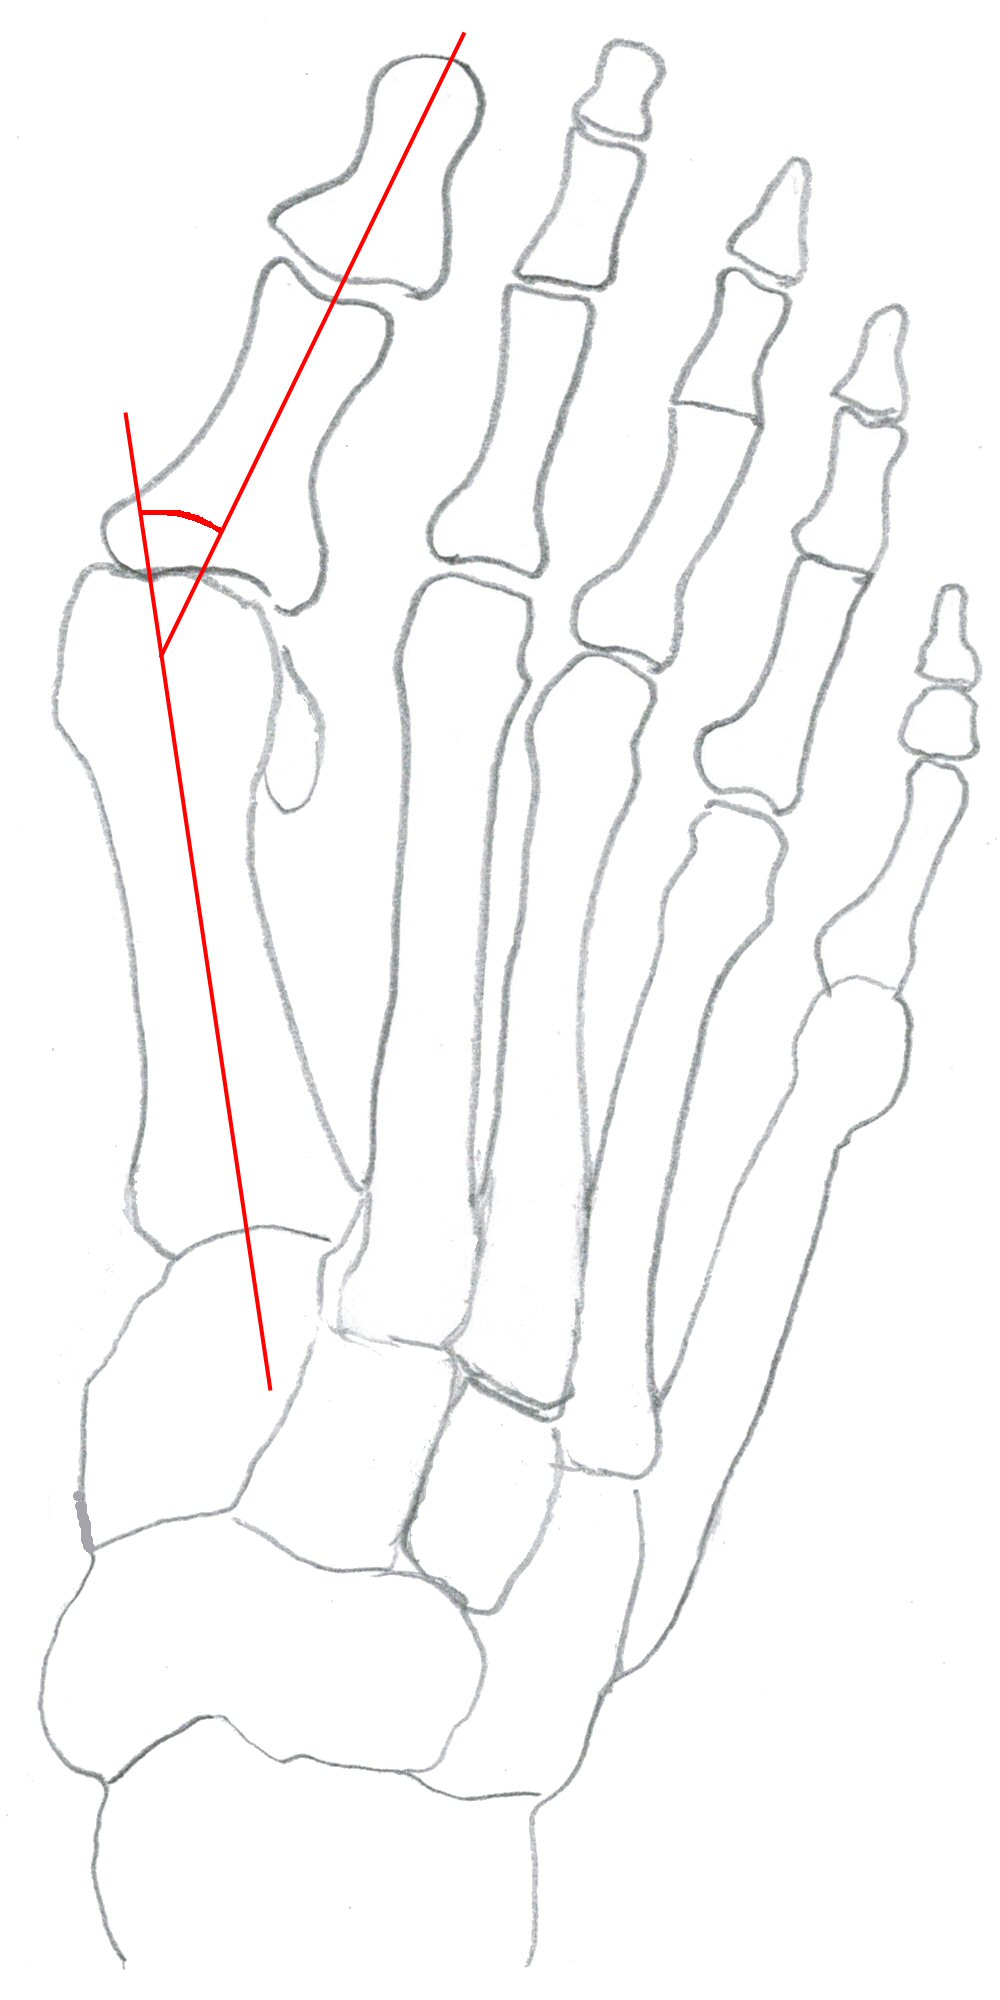

Hallux valgus-vinkel: vinkel mellan metatarsale 1 och grundfalang dig 1, normalt ≤ 15°.

Fot med hallux valgus, markerad hallux-valgusvinkel